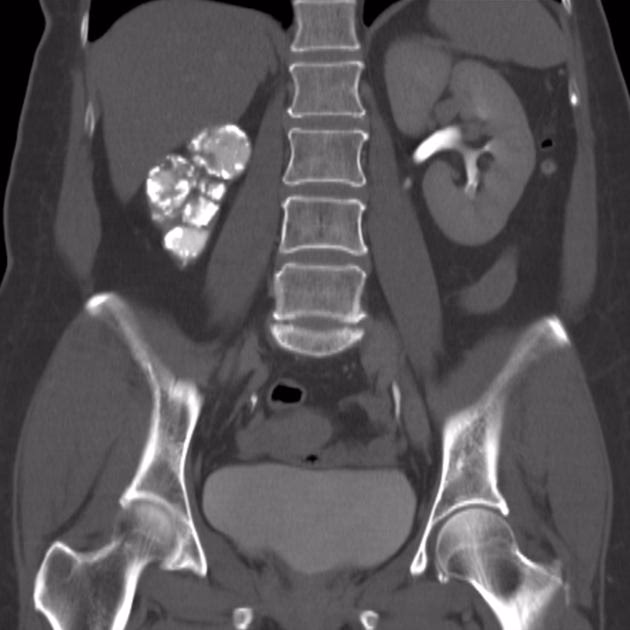

- CT-scanning: En CT-scanning af bughulen og urinvejene er afgørende for at visualisere nyrernes struktur. Den kan afsløre typiske tegn på nyretuberkulose, såsom forkalkninger, bylder (abscesser), arvæv, der forårsager forsnævringer (strikturer) i urinlederne, og udvidelse af nyrebækkenet (hydronefrose).